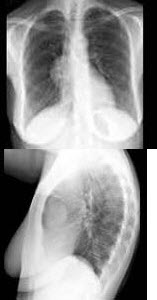

根据图象提示,重症肌无力患者做X线胸片检察的目的是( )

A:检察是否合并有肺部感染

B:检察是否有异位甲状腺

C:检察是否有肺结核

D:检察是否有膈肌麻痹

E:检察是否有胸腺瘤